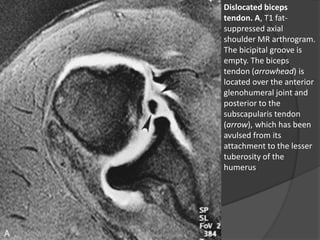

Dislocated biceps

tendon. A, T1 fat-

suppressed axial

shoulder MR arthrogram.

The bicipital groove is

empty. The biceps

tendon (arrowhead) is

located over the anterior

glenohumeral joint and

posterior to the

subscapularis tendon

(arrow), which has been

avulsed from its

attachment to the lesser

tuberosity of the

humerus

• 38.

Lacerações, Degeneração e Luxaçãodos Tendões  Cabeça Longa do Bíceps – Luxação:  Ligamento umeral transverso: ○ Liga as tuberosidades maior e menor do úmero, mantendo o tendão da cabeça longa do bíceps no lugar. ○ Necessário romper-se para haver luxação ou subluxação do tendão da cabeça longa do bíceps.  Na luxação → deslocamento medial do tendão para dentro da articulação → laceração do tendão do subescapular. Dr. Emanuel R. Dantas

• 39.

Dislocated biceps tendon. A,T1 fat- suppressed axial shoulder MR arthrogram. The bicipital groove is empty. The biceps tendon (arrowhead) is located over the anterior glenohumeral joint and posterior to the subscapularis tendon (arrow), which has been avulsed from its attachment to the lesser tuberosity of the humerus Dr. Emanuel R. Dantas